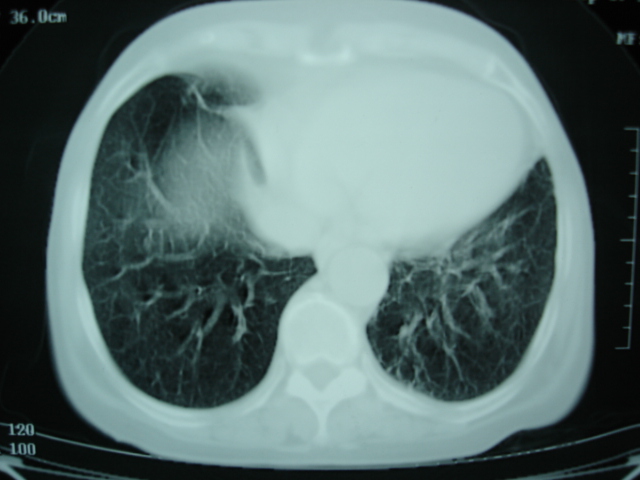

以下是引用卜一在2009-9-7 19:51:00的发言:[br][br] 1 左侧胸内甲状腺占位-多考虑甲状腺腺瘤! 2、左肺门占位-建议增强扫描以便明确性质。 3 慢支并感染! [br]

以下是引用shibing在2009-9-7 20:40:00的发言:[br]左侧胸内甲状腺占位-多考虑甲状腺腺瘤! 2、左肺门占位-建议增强扫描以便明确性质。 3 慢支并感染! [br]